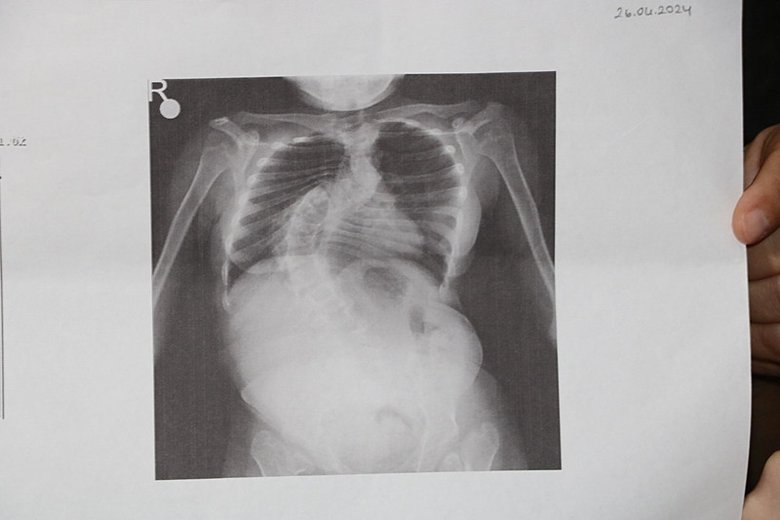

Son dakika İzmir haberleri... İzmir'de Fadime (48)- Abdullah Akbay (55) çiftinin skolyoz (omurga eğriliği) hastası kızları Kardelen Akbay'ın (16) tedavisi için gerekli 4 milyon TL'nin toplanması için valilik onaylı kampanya başlatıldı. Skolyoz eğrilik derecesi 96'ya çıkan Kardelen Akbay, "Omuriliğim akciğerimi içine girmeye başlamış. Derecem biraz daha yükselirse, ameliyat şansım da kalmayacak ve hayati riskim artacak. Ameliyatın maliyeti 4 milyon TL ve bir an önce bu parayı toplamamız gerekiyor" dedi.

Kardelen Akbay'a, 5 yaşında skolyoz tanısı konuldu. Düzenli aralıklarla hastane kontrolüne götürülen Kardelen Akbay'ın skolyoz eğrilik derecesi, gün geçtikçe arttı. Akbay'ın kontrol sürecine pandemi döneminde 1 yıl ara verildi. Daha sonra kontrole götürülen Akbay'ın skolyoz eğrilik derecesinin yüzde 85'e kadar çıktığı belirtildi. 1,5 yıl boyunca doktor aradıklarını ancak riskli olduğu gerekçesiyle kızını ameliyat edecek bir doktor bulamadıklarını söyleyen baba Abdullah Akbay, bu süreçte Kardelen'in skolyoz eğrilik derecesinin 96'ya ulaştığını belirtti.

Araştırmaları sonucu ameliyatı kabul eden bir doktor bulduklarını, kızının tedavisi için gerekli olan 4 milyonu bulmak için valilik onaylı kampanya başlattıklarını ifade eden Akbay, "3 ya da 6 ayda 1 kızımı kontrole götürüyordum. Skolyoz artmaya devam etti. Pandemi de kontrole götürmeme gerek olmadığı söylendi. Ancak 1 yıl sonra götürdüğümde doktor hastalığın tahmininden fazla ilerlediğini ve skolyoz eğrilik derecesi 85'e çıktığı için ameliyat edemeyeceğini söyledi. Daha sonra farklı doktorlar aramaya başladık. Birçok doktor ameliyat edemeyeceğini söyledi. 1,5 sene geçti, son gittiğimiz doktor ise 'Skolyoz derecesi 96'e çıkmış ve akciğerleri ile iç içe girmiş, ölümcül riskleri var ve ameliyat edemem' dedi. Bu süreçte kahroldum, hep bir çare için doktor aramaya devam ettim" dedi.